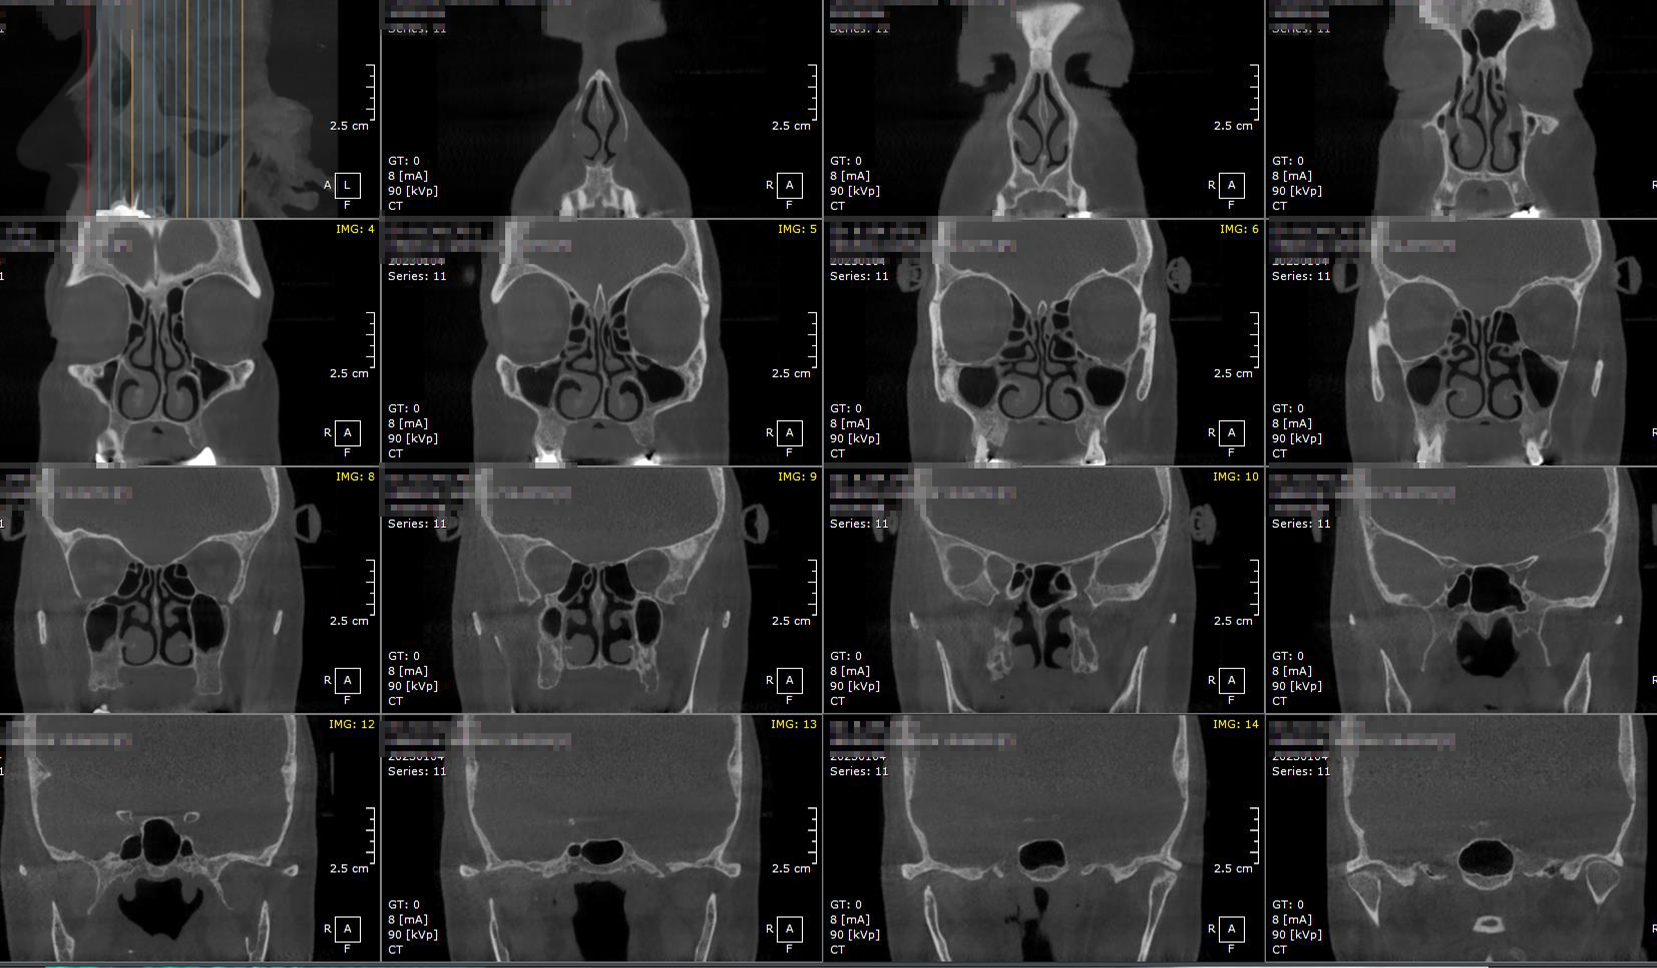

Senos Paranasales